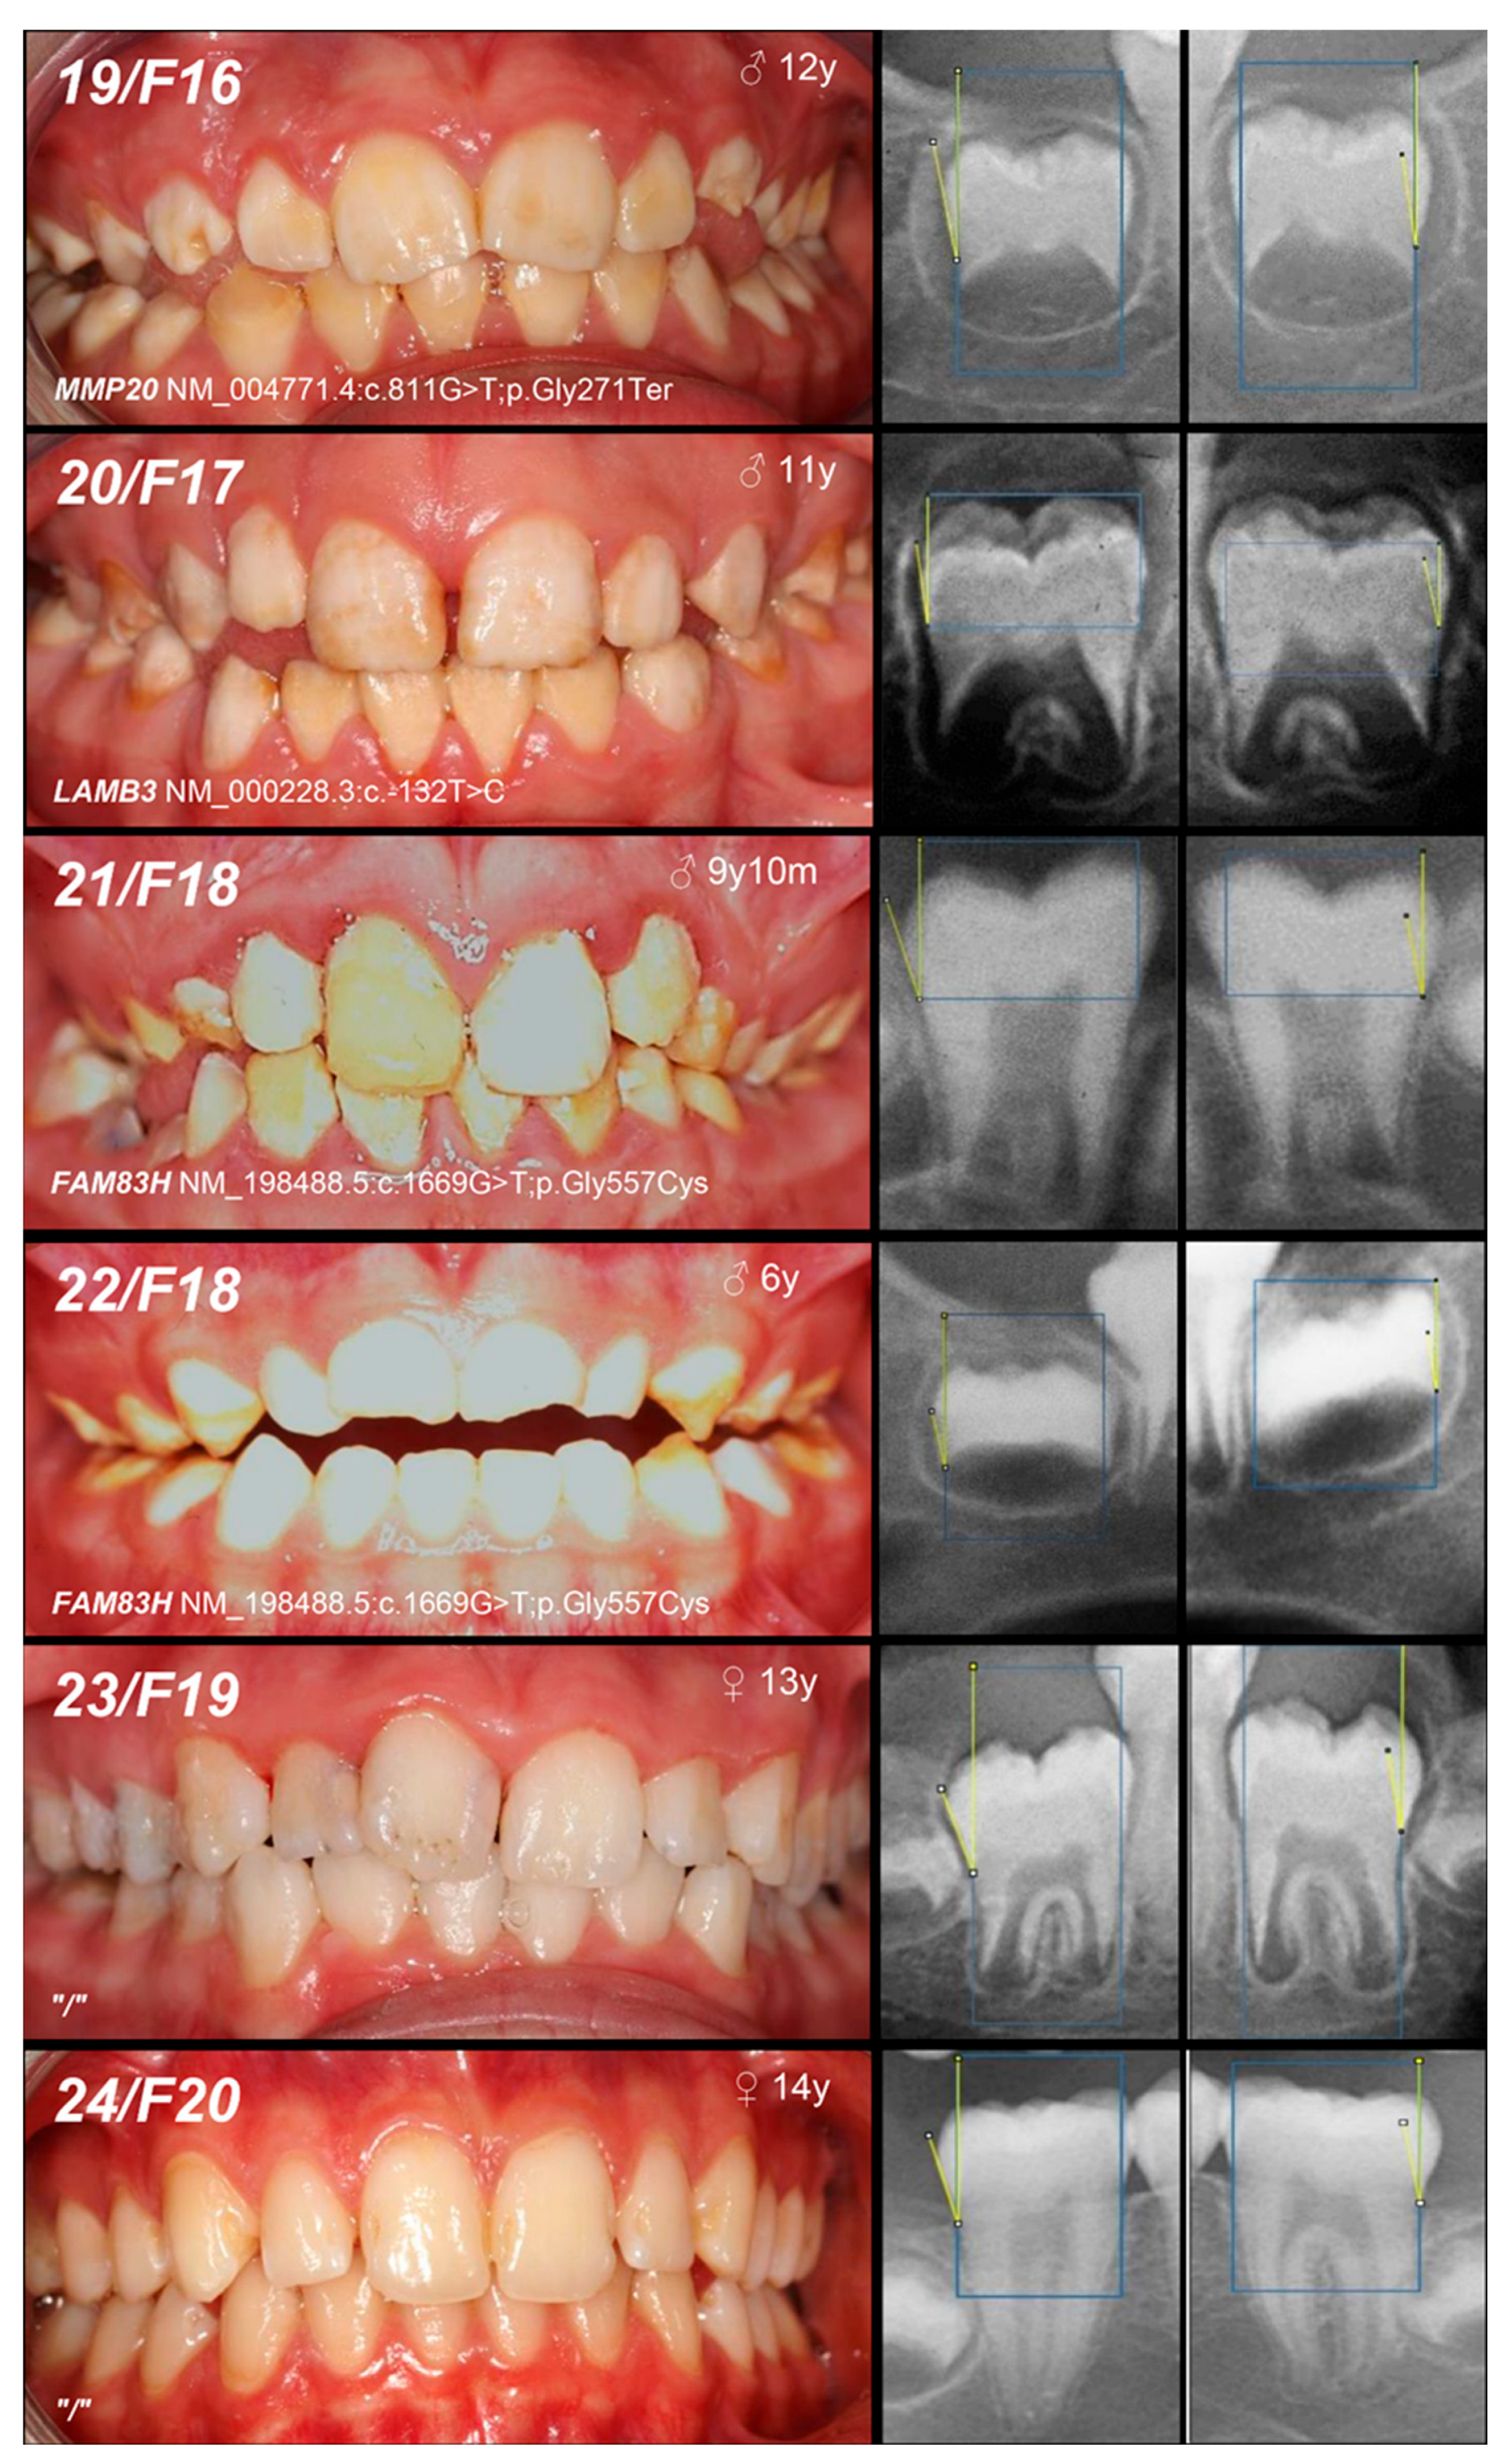

| Patient (n) Family (n) | Phenotype | OMIM, Mode of Inheritance, Gene Affected | Gene Variant | Zyg. | Protein Outcome | References | Fam. Segreg. | ACMG |

|---|---|---|---|---|---|---|---|---|

| 16, F14 | Hypomineralized (pigmented hypomature) | IIA2, AR, MMP20 | c.540T>A | +/− | p.Tyr180Ter | [28] | Mo (UC) Fa (U) | likely pathogenic (PVS1: very strong, PM2: moderate) GnomAD: 0.00000707 |

| 17, 18, F15 | c.811G>T | +/− | p.Gly271Ter | novel | Mo (AC) Fa (U) | likely pathogenic (PVS1: very strong, PM2: moderate) | ||

| +/− | ||||||||

| 19, F16 | +/− | Mo (UC) Fa (U) | ||||||

| 20, F17 | Hypoplastic (pitted) | IA, AD, LAMB3 | c.-132T>C | +/− | / | novel | Mo (AC) Fa (U) | VUS (PM2: moderate, BP7: supporting) |

| 21, 22, F18 | Hypomineralized (hypocalcified) | IIIA, AD, FAM83H | c.1669G>T | +/− | p.Gly557Cys | [29] | MoFa (NA) | benign (BA1: stand-alone, BS1: strong, BS2: supporting, BP4: supporting, BP6: supporting) * |

| +/− |